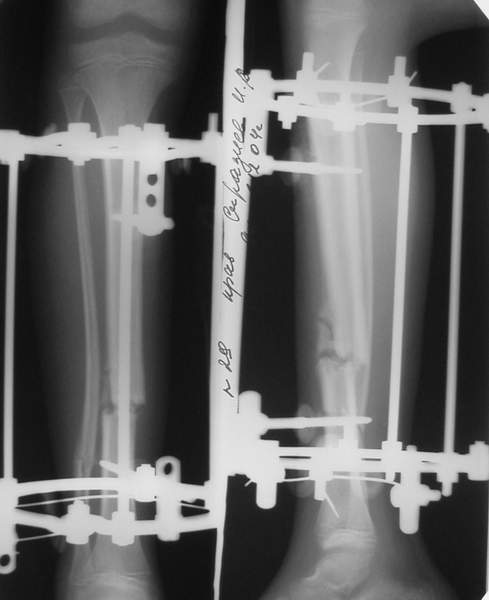

2

3a

3b

3c

В аттачте № 3 - один из примеров полукольцевого аппарат...

Это уже я баловался.

Итог? Работы больше (по времени и

интраоп "подгонке"), срастается также, а особого преимущества по сравнению с

"чиста" кольцевым (вес, удобство ношения и пр.) - я, по крайней мере,

не нашел.

Теперь не балуюсь.

Может быть зря?